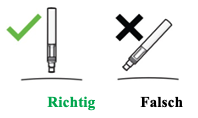

5. So halten Sie den Pen: